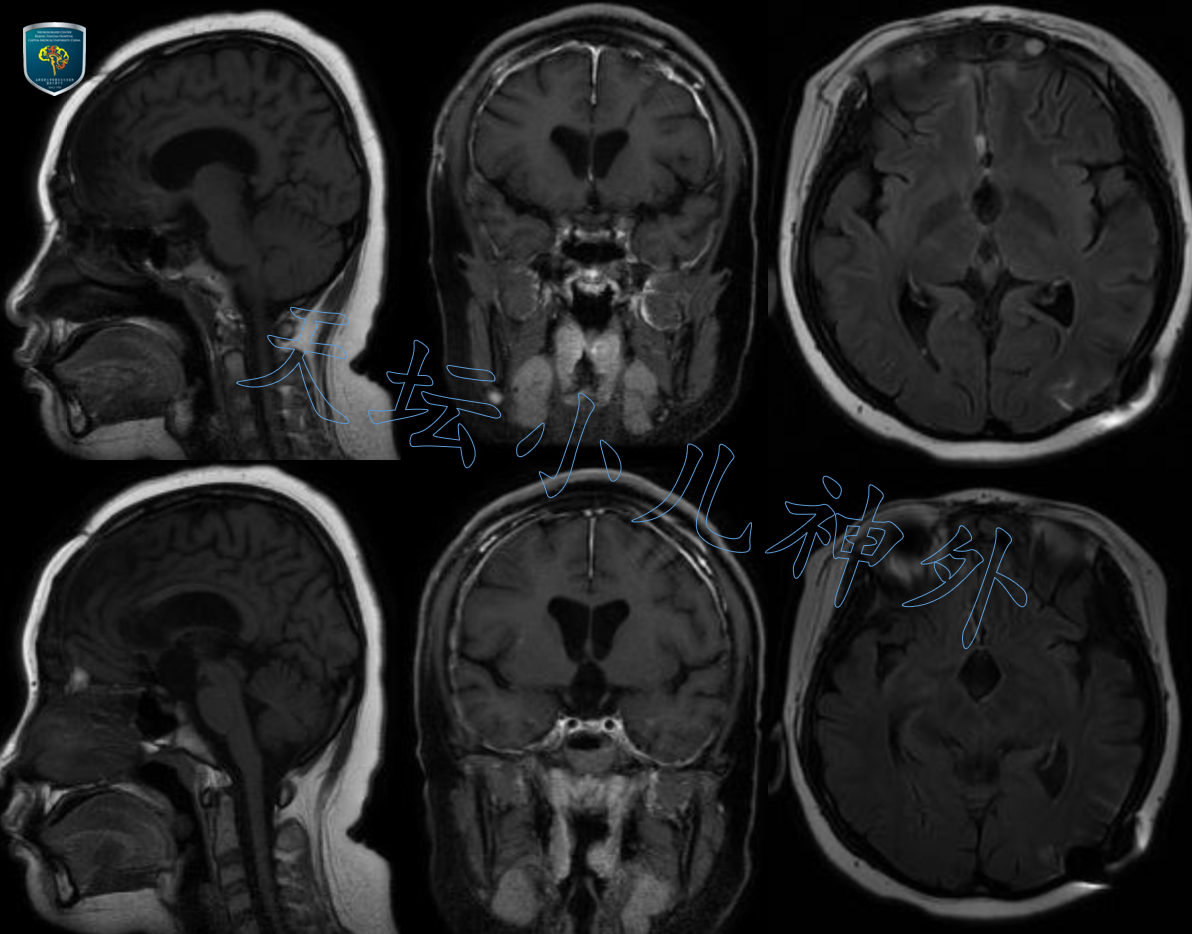

2020年11月接诊一例来自山东莒县12岁女性患儿(158cm,52.0kg),主诉:间断头痛1月,双眼视力下降5天。当地医院检查示巨大鞍区占位,遂来我院就诊。门诊查体示:神清语利,自主体位,双眼视力下降,眼前20cm数指,双瞳等大、光反应灵敏,余神经系统查体阴性。术前激素水平正常;头颅CT平扫显示:鞍区囊实性占位伴钙化,梗阻性脑积水伴室旁水肿,颅咽管瘤?(图1)。MRI显示:蝶鞍扩大,鞍上囊实性占位突入第三脑室,视交叉受压,长圆形混杂信号影,边界清晰,大小约40*25*25mm,囊壁不均匀强化,颅咽管瘤可能性大(图2)。